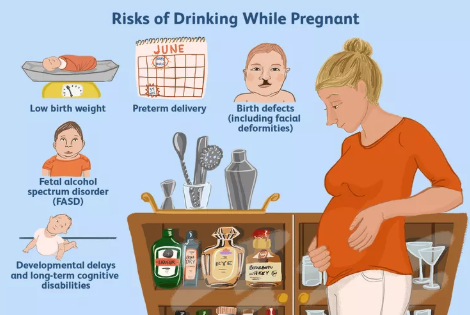

Uống Rượu Khi Đang Cố Gắng Thụ Thai: Những Điều Cần Biết Dựa Trên Cơ Sở Khoa Học

Việc sử dụng rượu trong giai đoạn cố gắng thụ thai là một chủ đề